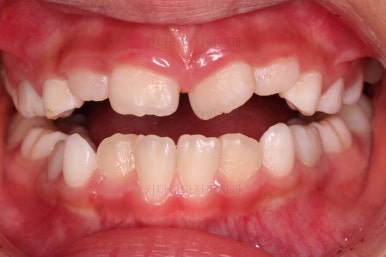

벌써 치료가 종료되었네요ㅎㅎ

총 4개월 걸렸습니다.

반대교합만 고쳐준 것이 아니라 기왕 하는김에 치열을 가지런히 해줬고요.

(아래 치열은 장치를 부착해주지도 않았는데 자연스럽게 처음보다 가지런해졌죠? ^^)

부산어린이반대교합 전후사진을 비교해 볼게요.

4개월만에 원하는 목표를 달성했고 충치도 다 치료했고 무사히 이민을 가실 수 있었답니다.